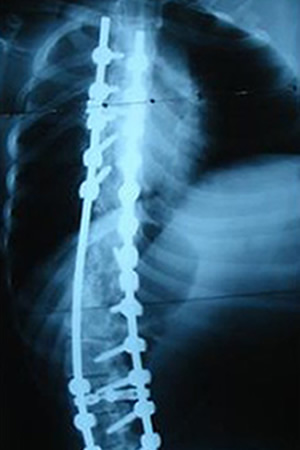

Grafilerle Skolyoz